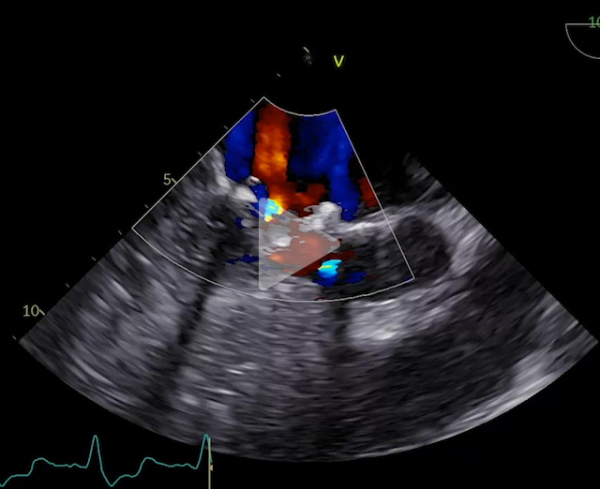

Voici son échocardiographie

Vidéo 2 : échocardiographie 2D en incidence parasternale grand axe avec doppler couleur

- Patient de 40 ans avec une CMH sarcomérique (mutation HTZ MYBPC3) avec épaisseur maximale en antéro-septo-basal à 33mm en IRM, associée à une obstruction sous aortique significative (GD max 77 mm Hg au Valsalva). Découverte d’une insuffisance mitrale (IM) sévère mixte organique sur prolapsus de P2 et fonctionnelle sur un SAM (mouvement systolique antérieur de la valve mitrale)

Vidéo 8 : échocardiographie 2D transoesophagienne sans et avec doppler couleur en incidence 3 cavités à 120°

Vidéo 9 : échocardiographie 2D transoesophagienne sans et avec doppler couleur en incidence 3 cavités à 120°

Il s’agissait d’une hémolyse mécanique en lien avec l’obstruction sous aortique (Gradient max 68 mm Hg) favorisée par un SAM de la valve mitrale à l’origine de la persistance d’une IM de haut grade. On suspectait notamment un SAM de néo cordage. Un contact direct entre hématies et anneau prothétique à l’origine d’un stress mécanique est possible aussi mais plus anecdotique.

L’ETO n’avait pas retrouvé de fuite péri plastie mitrale.